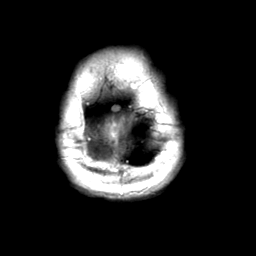

Meningioma, MR Study #2 -- Slice #21

[Home][Help][Clinical] Slice 21